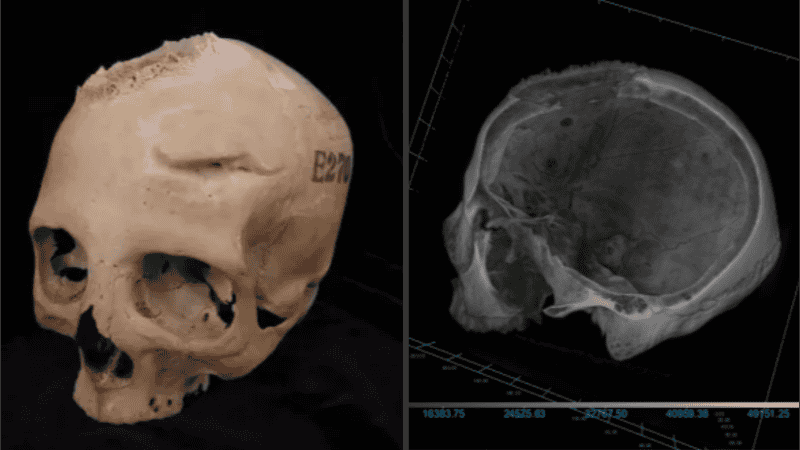

Científicos encontraron una serie de marcas en un antiguo cráneo egipcio, las cuales sugieren una intervención quirúrgica oncológica en el Egipto de hace 4.300 años. Los hallazgos provienen del examen del cráneo de un hombre de unos 30 años del año 2500 a.C. y de una mujer de unos 50 años del año 500 a.C.

Si bien ambos tenían huesos dañados, lo que demuestra que probablemente padecían cáncer cerebral, también tenían marcas de herramientas. Los investigadores dijeron que eran una prueba de que los curanderos intentaron operar tumores cerebrales, según publicó el medio británico The Sun.

El profesor Edgard Camaros, de la Universidad de Santiago de Compostela, en España , dijo: "Esta es una evidencia única de cómo la medicina egipcia antigua habría intentado abordar o explorar el cáncer. Es una nueva perspectiva extraordinaria para comprender la historia de la medicina".

Se sabía según explicaron que los egipcios eran buenos con el metal y usaban cobre, hierro y oro para hacer decoraciones. También experimentaron con la medicina reparando las caries con empastes metálicos, entablillando huesos rotos y usando miel y plantas para curar enfermedades. Los hallazgos sugieren que los antiguos egipcios entendían el cáncer pero no podían tratarlo.

La investigadora Tatiana Tondini añadió: "Aunque los antiguos egipcios eran capaces de tratar fracturas complejas, el cáncer seguía siendo una frontera del conocimiento médico".